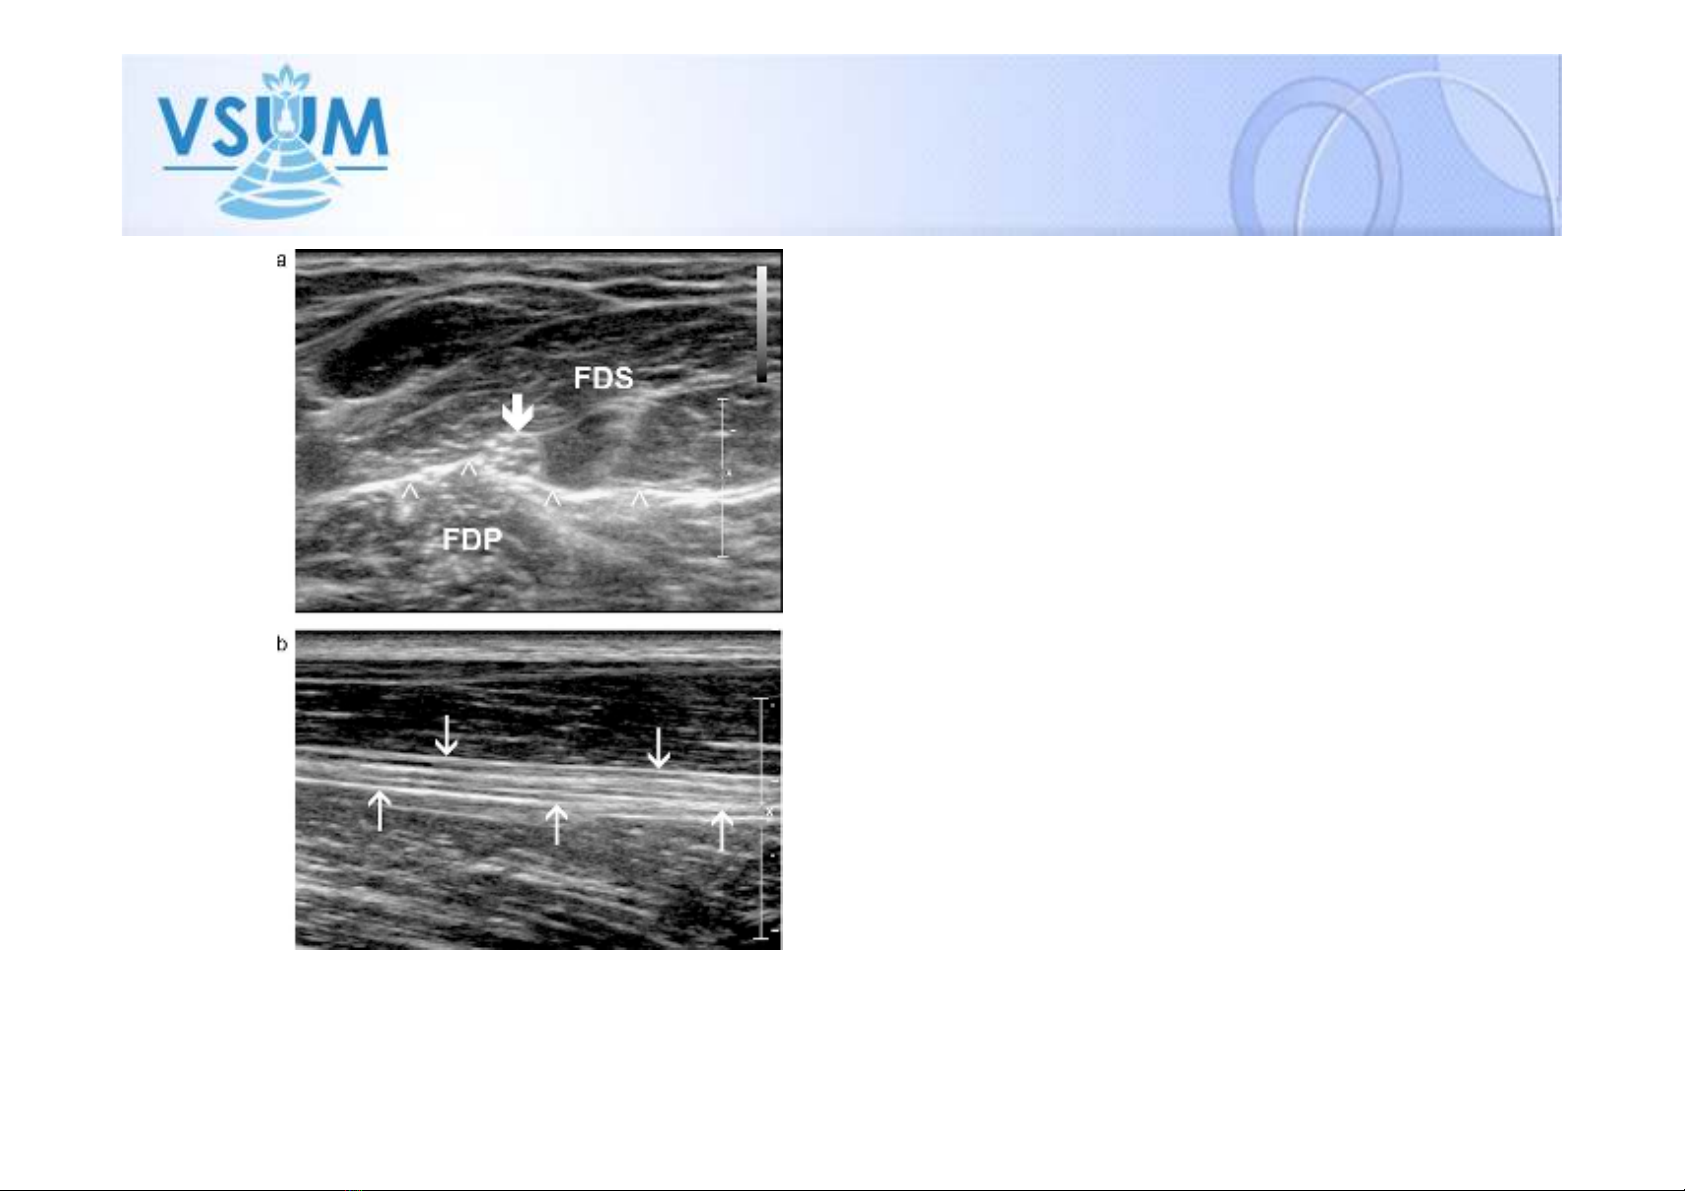

• Có hình ảnh như tổ ong trên

mặt cắt ngang dây thần kinh

• Hình dải sợi song song trên

mặt cắt dọc dây thần kinh